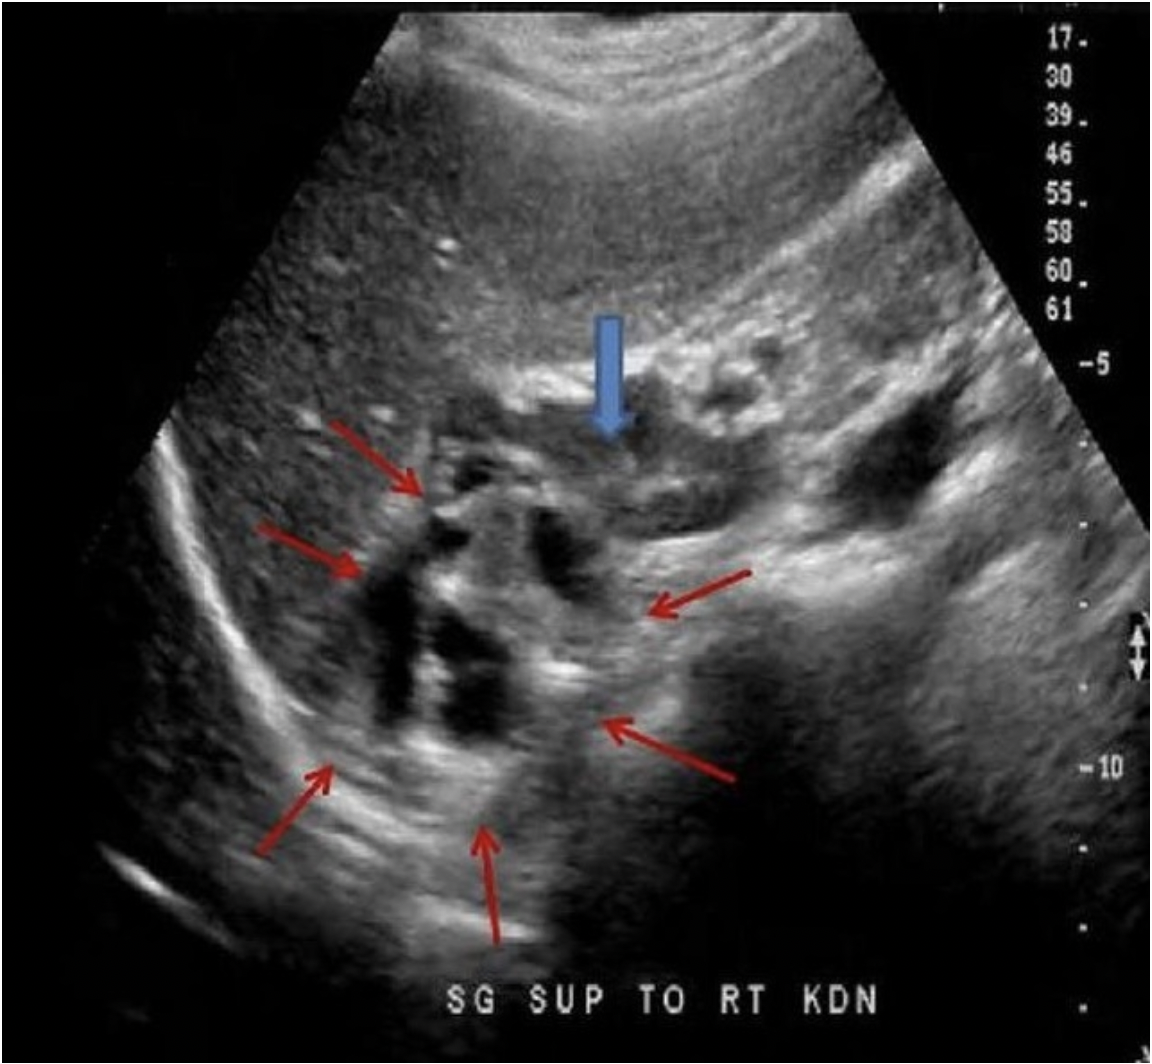

The blue arrow indicates the adrenal gland in a 30 yr old male with a palpable flank mass and no other related history. Which of the following best describes the findings on the image demonstrated by the red arrows?

A. complex adrenal mass located superior to the gland, most likely cortical carcinoma

Adrenal cortical carcinoma usually presents as a complex adrenal mass. The solid and cystic components cause a very irregular appearance.